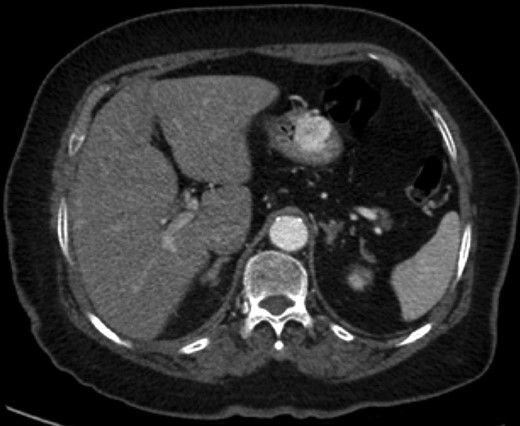

An 88-year-old female presented with 5 days of weakness and dyspnea, severe anemia (hemoglobin of 46 g/l), and no evidence of bleeding on history. Physical examination was remarkable for a blood pressure of 83/48, and black stool on rectal examination. Endoscopy demonstrated a 4-cm submucosal mass in the distal body of the stomach. The mass had central ulceration and a visible vessel, not actively bleeding. The presumptive diagnosis was GIST. CT demonstrated a 2.5 × 1.9 cm well-circumscribed, partially exophytic, arterially enhancing lesion. She underwent wedge resection of the greater curvature. She was discharged home on postoperative day 3 without complication. Pathology found a lobulated tumor composed of glomus cells in the submucosa and muscularis propria. The cells were positive for α-smooth muscle actin, caldesmon and vimentin. There was focal positivity for synaptophysin and CD34. These are consistent with a GT.

A 70–year-old male presented with light headedness, shortness of breath and 2 days of bright red blood per rectum progressing to melena. His hemoglobin was 92 g/l, a decrease from 144 g/l 10 days prior. Upper endoscopy demonstrated a 3-mm polyp in the duodenal cap (biopsy would be reported as a completely excised carcinoid tumor). Colonoscopy demonstrated a bleeding, edematous region in the ascending colon. Biopsy was non-diagnostic. CT demonstrated a 2.3 × 1.6 cm ascending colon lesion with hyperenhancement in the arterial phase and persistent enhancement in the portal venous and delayed phases. On octreotide scan, the lesion had intense uptake, consistent with a carcinoid. The clinical picture was in keeping with two synchronous primary carcinoid tumors. Laparoscopic converted to open right hemicolectomy was performed without complication. Final pathology demonstrated a GT with negative margins, 26 negative lymph nodes, 1 mitosis per 50 hpf, no vascular invasion and absence of necrosis. Follow-up for the colonic GT will include a colonoscopy and abdominal CT 1 year following surgery, as well as chromogranin A level every 6 months. Chromogranin A was mildly elevated preoperatively. For his duodenum, he will be followed with Esophagogastroduodenoscopy +/− endoscopic ultrasound (EUS) every 3–6 months initially.

Endoscopic findings of gastric GTs are that of a submucosal mass, typically in the antrum or distal body, with either normal mucosa or ulceration [3, 4] (Fig. 1). CT shows a well-defined submucosal tumor with a clear margin, strong enhancement in the arterial phase, and prolonged enhancement in the delayed phase [4, 5] (Fig. 2). Often confused with GIST, the distinguishing features are that the density of GISTs is lower than that of GTs, and GISTs do not exhibit prolonged enhancement in the delayed phase [5]. On EUS, the GT is found in the fourth endosonographic layer, with a heterogeneous appearance. In one small study of seven gastric GTs, six demonstrated the characteristic ‘peripheral halo’ sign around the tumor [5].